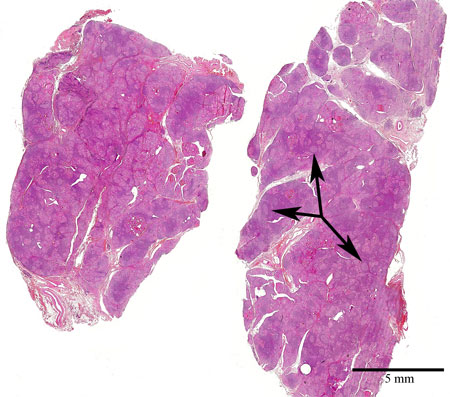

Snitt från sköldkörtel. Pilarna visar på germinala centra. Man antar att det är fråga om en autoimmun sjukdom där lymfocyterna i organismen så småningom förstör sköldkörtelvävnaden. Man talar om Hashimotos sjukdom (Thyreoiditis Hashimoto).

Översikt, H&E.